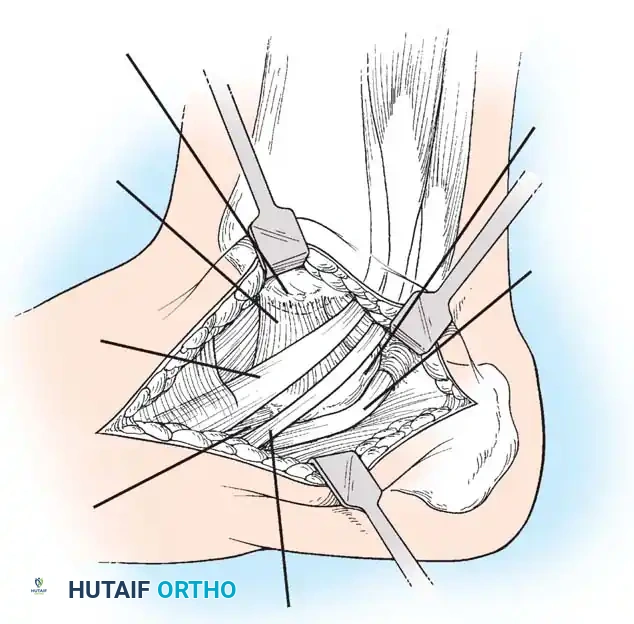

🔪 Surgical Technique 79-6: The Kidner Procedure

1. Incision and Exposure

-

Incision: Begin the skin incision 1 to 1.5 cm inferior and distal to the tip of the medial malleolus. Arch the incision slightly dorsalward, peaking directly over the medial prominence of the accessory navicular, and slope it distally to the base of the first metatarsal.

-

Dissection: Carefully dissect through the subcutaneous tissues. Identify and ligate the plantar communicating branches of the saphenous venous system. Protect the terminal branches of the saphenous nerve.

-

Tendon Identification: Identify the posterior tibial tendon as it approaches the accessory navicular.

-

Tendon Exposure: Identify the dorsal and plantar margins of the PTT approximately 2 cm proximal to the accessory navicular. Expose the tendon distally, ending at the bone.

Surgical Warning: It is imperative to expose the entire tendon without disturbing the portion extending plantarward toward its multiple insertions on the cuneiforms and metatarsal bases. Preserving these plantar slips maintains the structural integrity of the midfoot.